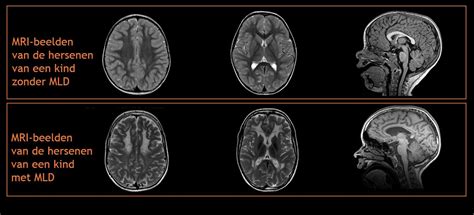

Op grond van het klinische beeld (ontwikkelingsachterstand, kleine lengte en hoofdomvang) kan het FOXG1-syndroom vermoed worden. Oriënterend bloedonderzoek laat doorgaans geen bijzonderheden zien. De diagnose kan gesteld worden door middel van genetisch onderzoek, waarvoor een buisje bloed nodig is. Bij kinderen met een ontwikkelingsachterstand wordt vaak een MRI-scan gemaakt om afwijkingen aan de hersenen te onderzoeken. Bij kinderen met het FOXG1-syndroom is de hersenbalk (corpus callosum) vaak onderontwikkeld (dysgenesie) en ziet het hersenoppervlak er anders uit met minder bollingen (gyri) en inkepingen (sulci).